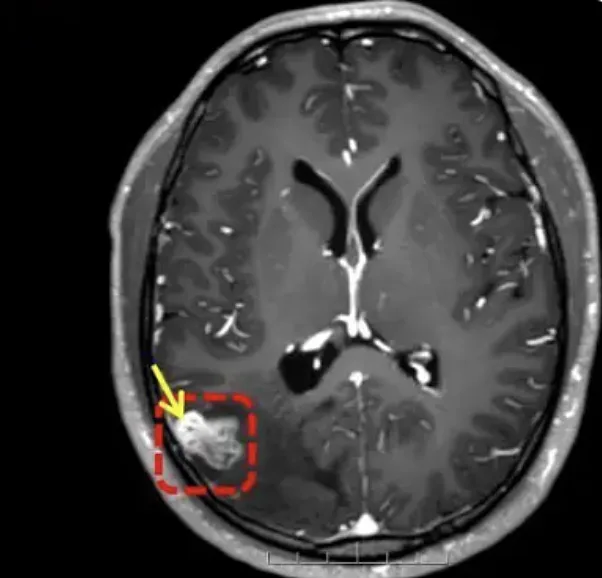

עם זאת, בבדיקת MRI שנערכה באפריל 2024 נמצא במוחו גוף זר. בשלב זה לא היה ברור אם מדובר בטפיל חי או בממצא חריג אחר, אך האיש החליט שלא לעבור ניתוח והמשיך בשגרת חייו.

כשנה לאחר מכן האיש חווה החמרה פתאומית במצבו. הוא סבל מהתכהות ראייה, הקאות, קצף לבן ועוויתות חזקות בגוף. הוא פונה מיד לבית החולים, שם התברר כי במוחו התפתחה תולעת טפילית באורך 18 ס"מ.